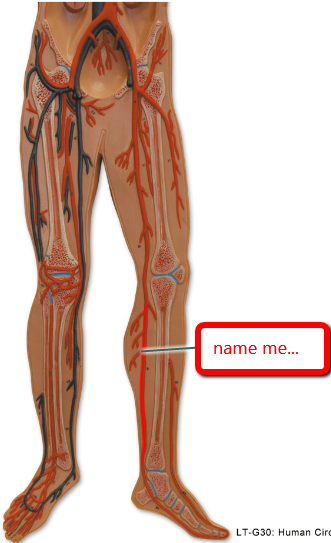

Anterior tibial artery/vein

Posterior tibial artery/vein

Femoral artery/vein

Great saphenous vein

Popliteal artery/vein